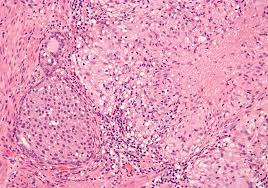

방광염(Bladder Inflammation)은 방광 내막(방광 벽면을 덮고 있는 조직)의 염증을 나타내는 의학적 용어입니다. 방광 내막의 염증은 주로 소변 방출과 관련된 고통과 불편을 유발하며, 종종 소변 통증, 빈발 소변, 혈뇨(소변에 혈액 혹은 혈전 혼합), 저림 통, 소변 불편감 등과 같은 증상을 동반합니다. 방광염은 다양한 원인에 의해 발생할 수 있으며, 원인에 따라 적절한 진단과 치료 절차가 필요합니다.

5. 방광내경 (시스토스코피): 만약 의심스러운 경우, 방광내경 검사가 수행될 수 있습니다. 이 과정에서 유연한 관찰용 관을 통해 방광 내부를 직접 확인하고 염증, 결석, 기타 이상을 시각화합니다.